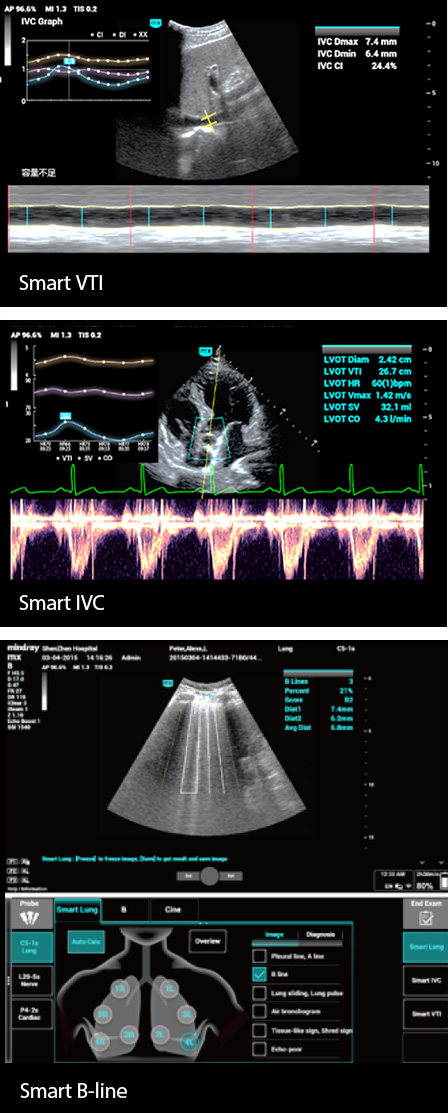

Por lo tanto, la monitorizaciÃģn estrecha de los fluidos de los pacientes y la gestiÃģn precisa de su volumen son de suma importancia. Sin embargo, la ecografÃa tiene la ventaja de ser mÃĄs intuitiva en la evaluaciÃģn dinÃĄmica de la funciÃģn cardiopulmonar y la hemodinÃĄmica de los pacientes y puede ayudar a los profesionales de cuidado de la salud de la UCI a tomar decisiones de tratamiento oportunas y observar los efectos del tratamiento en tiempo real.

Por lo tanto, la monitorizaciÃģn estrecha de los fluidos de los pacientes y la gestiÃģn precisa de su volumen son de suma importancia. Sin embargo, la ecografÃa tiene la ventaja de ser mÃĄs intuitiva en la evaluaciÃģn dinÃĄmica de la funciÃģn cardiopulmonar y la hemodinÃĄmica de los pacientes y puede ayudar a los profesionales de cuidado de la salud de la UCI a tomar decisiones de tratamiento oportunas y observar los efectos del tratamiento en tiempo real.